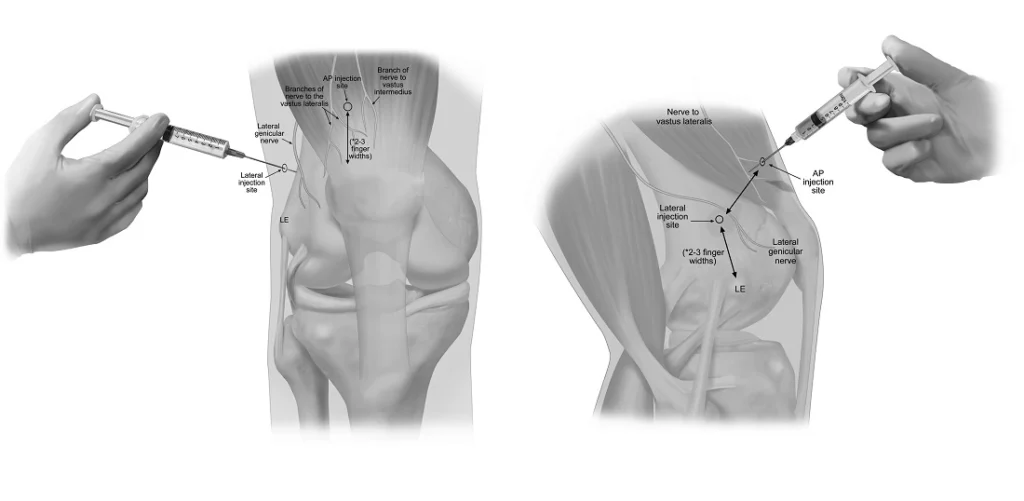

A genicular nerve block is not preparation given to the knee joint, which is more commonly known as an injection given to the knee joint. This procedure is intended to target the genicular nerves, which are very small and carry signals of pain from the joint to be relayed to the brain. The procedure involves very good knowledge of the area’s anatomy.

The practitioner finds the major SP sites around the knee region. Under the guidance of image intensification (usually fluoroscopy or ultrasound), a small needle is directed at the site around the SPs. A small quantity of local anesthetic is administered. This temporarily stops the transmission of pain signals.

If you seek the best Genicular Nerve Block Treatment doctor in Jaipur, understand that it is much more than injection treatment. It’s about a proper diagnosis, an attack on the right nerve, and outlining a plan that actually improves your life.

– Imaging-guided needle placement for greatly improved precision Safety, comfort, and accurate understanding of procedural outcomes. Specific follow-up guidance for physiotherapeutic exercises, strengthening, and maintaining healthy knees If your knee pain starts affecting your daily activities, and you are looking for a surgical alternative, then the “genicular nerve block” can prove helpful as the next pain-relieving solution, as it will also guide your ‘long-term plan’.